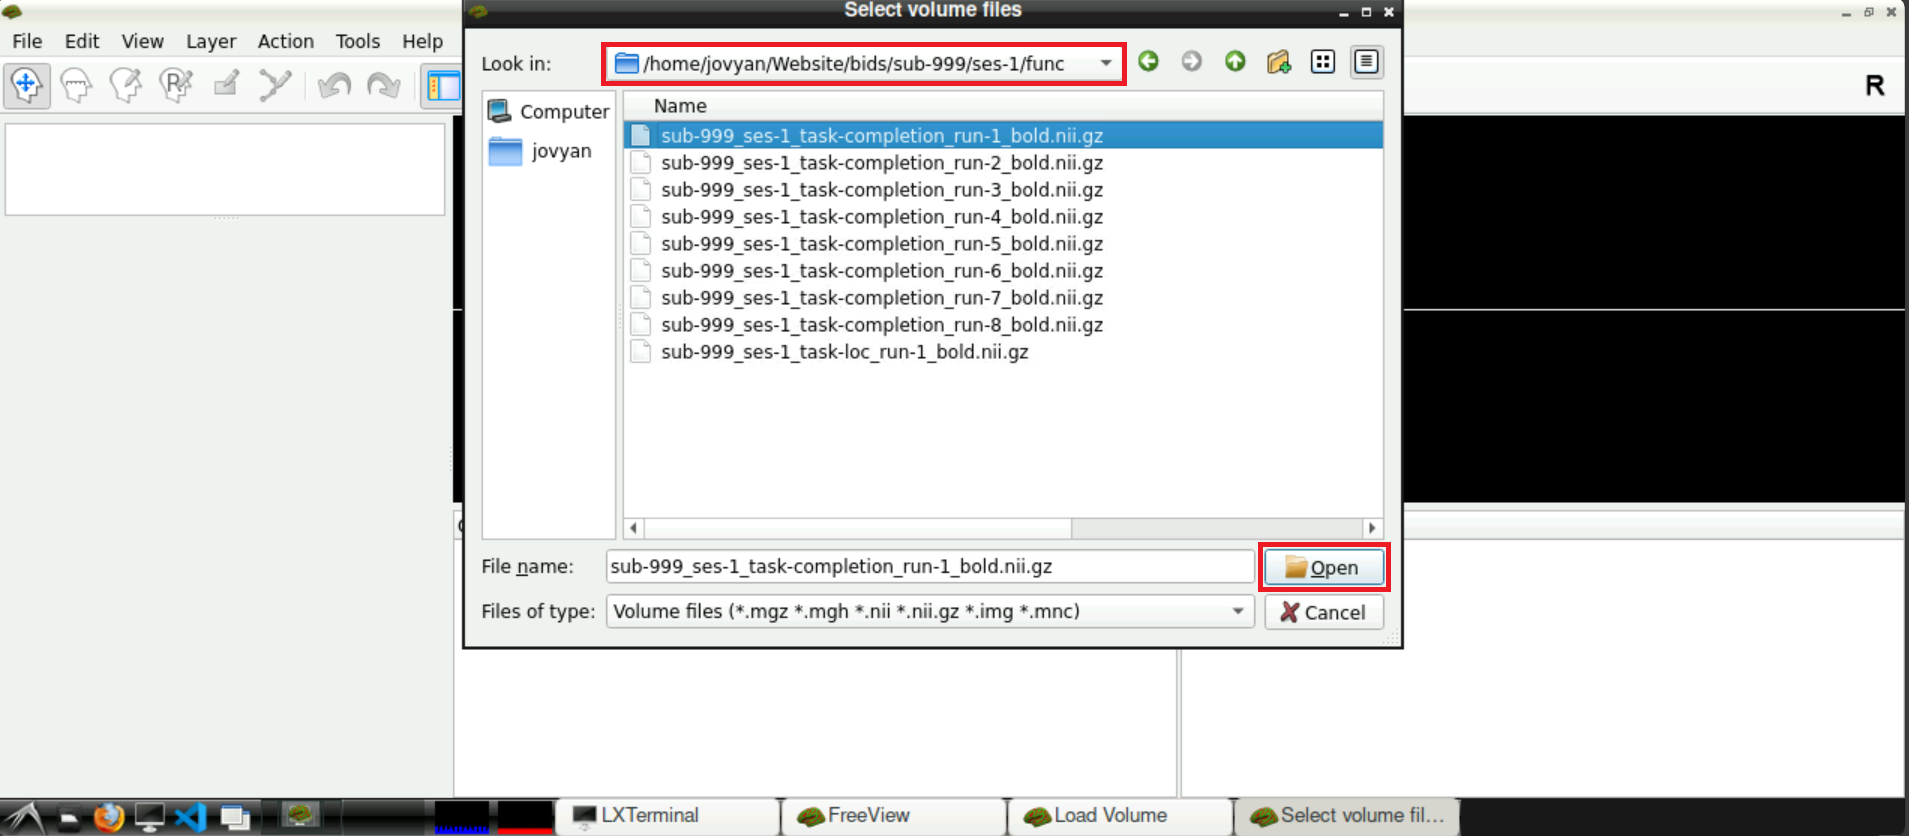

Navigate to your func directory in your BIDS, select one of the nifti files of one of the runs and press Open afterwards